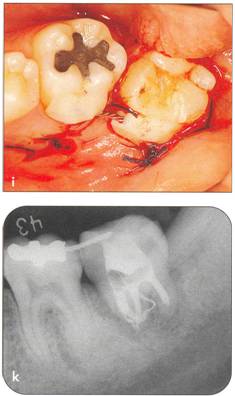

Fi 545e45f g 5-3h The extracted donor tooth. The form of the root and the amount of the periodontal ligament are not ideal. Fi 545e45f g 5-3i Suture of the gingival flap and fixation after transplantation. |

Fi 545e45f g 5-3j After transplantation. Fi 545e45f g 5-3k Three months after transplantation. Because healing of the pulp was not achieved, apexification was initiated. |